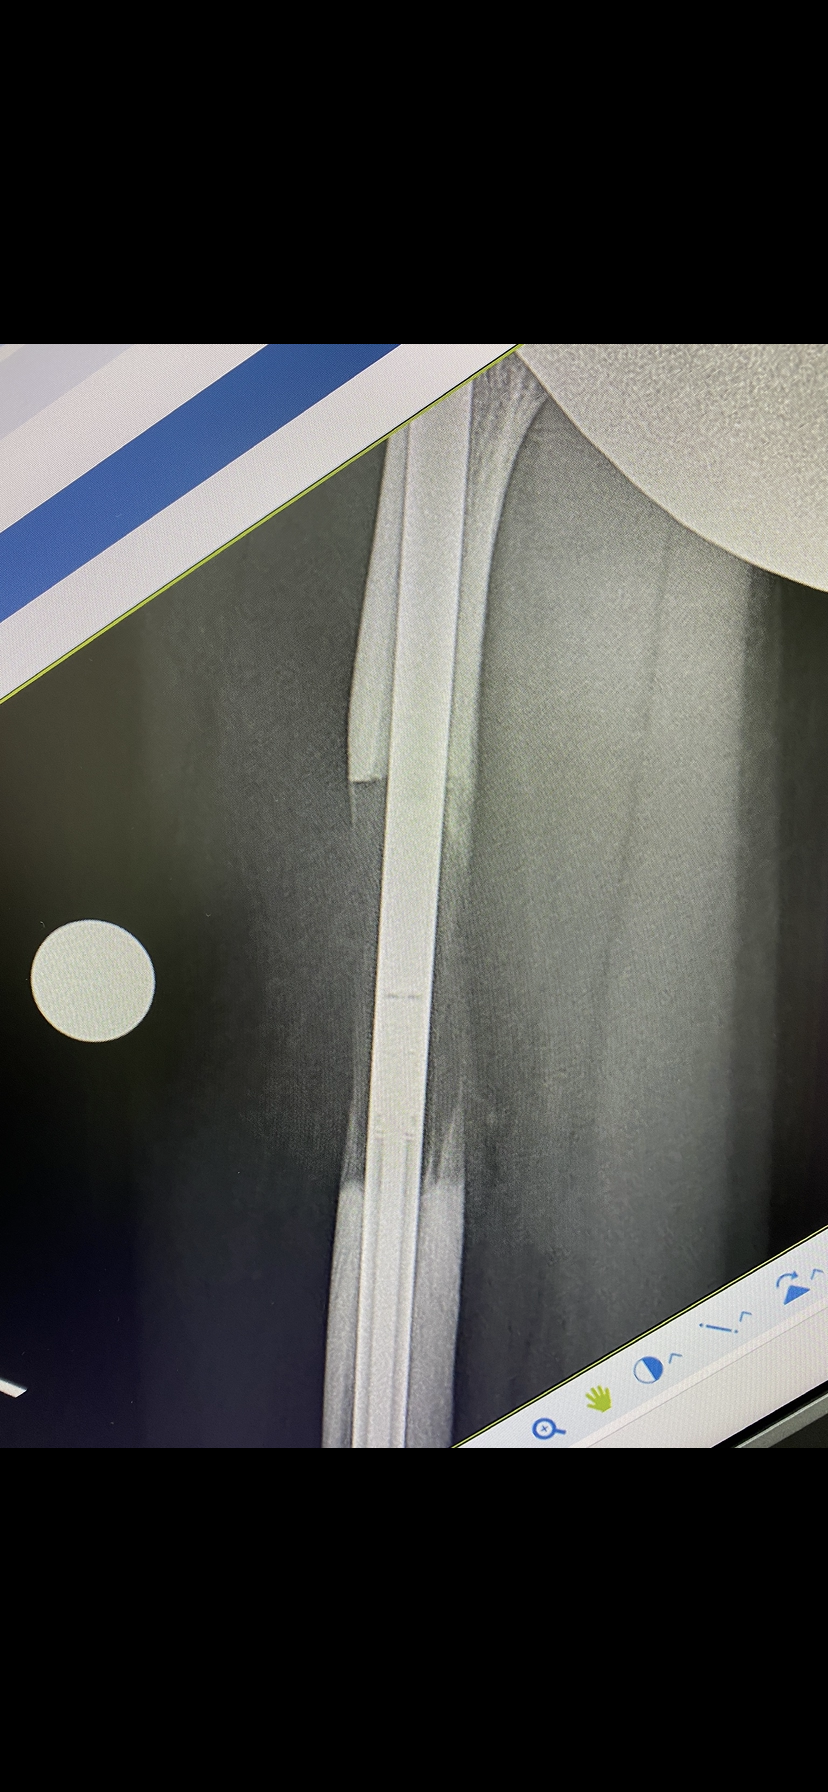

Precice nail (พรีใซส์ เนล) อุปกรณ์ที่ใส่ในโพรงกระดูก เพื่อยืดกระดูกออก

หลักการทางชีววิทยาคือ เมื่อมีการตัดกระดูกออกเป็นสองท่อน แล้วทำการค่อยๆดึงกระดูกให้ห่างออกจากกันช้าๆ วันละ 1 มม. โดยแบ่งการดึงออกเป็น 4 ครั้งต่อวัน ครั้งละ 0.25 มม. ร่างกายจะสร้างกระดูกใหม่เข้ามาเติมในช่องว่างได้เอง กระดูกใหม่ที่เกิดขึ้นมาเรียกว่า regenerate เมื่อดึงถึงจุดที่พอใจแล้วให้หยุดดึงได้ หลังจากนั้น regenerate จะค่อยๆแข็ง (consolidation) ขึ้นเรื่อยๆ ใช้เวลา 2 เดือนขึ้นไปหลังจากดึงเสร็จ เพื่อรอให้ regenerate แข็งเหมือนกระดูกปกติ กระดูกที่เกิดขึ้นมาใหม่จะมีความแข็งแรงและมีคุณสมบัติเหมือนกระดูกปกติทุกอย่าง

กระดูก femur ยืดได้สูงสุด 8 ซม. ยืดวันละ 1 มม. เริ่มยืดหลังผ่าตัดวันที่ 7 ใช้เวลายืดทั้งหมด 3 เดือน รอกระดูกติด (consolidate) อีก 3-5 เดือน จึงให้เดินได้โดยไม่ต้องใช้ไม้ค้ำยัน